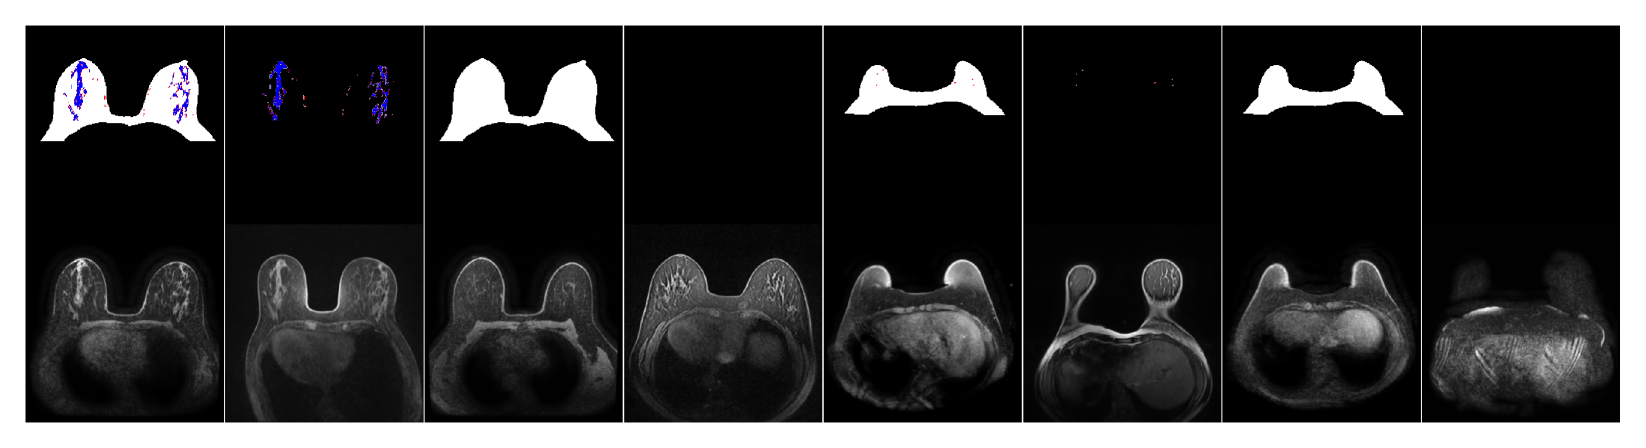

fig:samples_ablated

3.2 Sampling from Ablated Masks

We will next explore our model’s ability to be conditioned on a range of combinations of present or missing anatomical classes in input masks, following our mask-ablated training algorithm (Sec. 1.3). In Fig. LABEL:fig:samples_ablated we demonstrate the effect on generated images of ablating certain classes from an input mask for breast MRI (more examples, including for CT Organ, in Appendix D). For example, we see that constraining the blood vessels and fibroglandular tissue (BV+FGT) in breast MRI, yet keeping the breast free, results in images that have the latter two classes pre-registered while the breast shape varies, and vice-versa.

Notably, we also see that when the model is provided with an empty mask (unconditioned), it typically generates more anatomically realistic images than the unconditionally-trained model does (e.g., compare the bottom right image in Fig. LABEL:fig:samples_ablated to the rightmost image in Fig. LABEL:fig:eg_imgs), due to the mask-ablated training acting as self-supervised learning of more realistic object representations (somewhat analogous to MAE [He et al.(2022)He, Chen, Xie, Li, Dollár, and Girshick]; see Appendix B). This is important because the model has both the anatomical realism of a model trained with full mask guidance and the ability to generate new diverse samples without needing input masks.